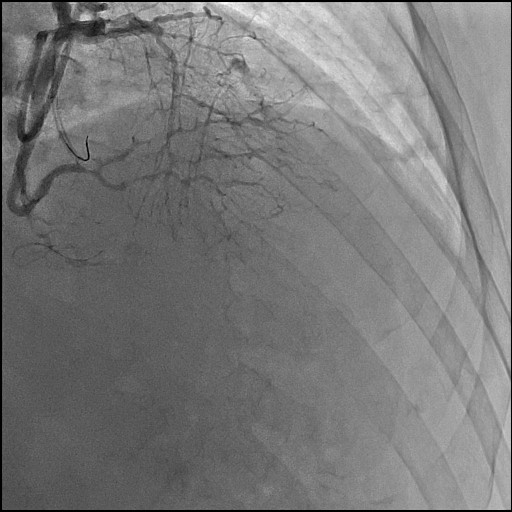

Re-attempted PCI for LAD CTO was planned. The procedure was performed with an 8-Fr, SPB 3.5 SH for the antegrade approach and a 6-Fr IMA for retrograde angiography. Primary antegrade approach was performed because there were no feasible collateral channels. Gaia Next 3 could penetrate the proximal cap of CTO. Since Gaia Next3 could not proceed into the CTO mid portion, the guide wire was escalated to Gaia Next 4. However, Gaia Next 4 advanced into extra plaque space beyond the CTO distal true lumen angiographically. Therefore, we decided to perform tip-detection (TD) method using intravascular ultrasound (IVUS). IVUS revealed that the guide wire proceeded into extra plaque from the CTO proximal portion, although the CTO entry was in the intra plaque space. At first, we tried TD-intra plaque tracking (IPT) in the CTO body. However, Conquest Pro 12 ST (CP-12ST) could not penetrate the CTO body. Therefore, we performed TD-antegrade dissection andreentry (ADR). Eventually, CP12 ST succeeded to puncture the distal true lumen supported by a Caravel. We implanted a drug-eluting stent, which resulted in successful revascularization.

Recently, TD-ADR has been established as a novel PCI technology in CTO. We successfully revascularized a vintage hard CTO lesion using TD-ADR. TD-ADR is suitable treatment option in CTO PCI if there are no feasible collateral channels.